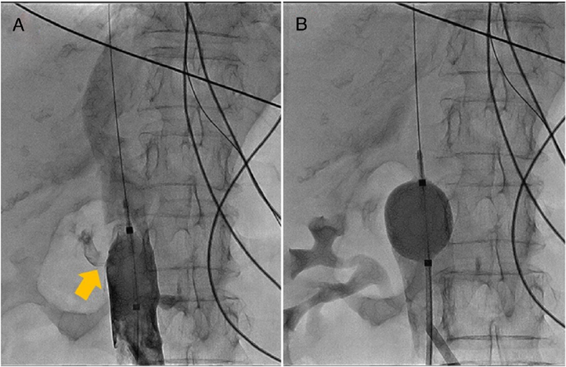

Figura 1 Imagen inicial de la perforación de la vena cava. A. Protrusión del catéter de ecocardiografía intracardiaca a través de la pared de la vena cava inferior (estrella azul). Se observa medio de contraste extravasado en el trayecto del catéter. B. Inyección de contraste una vez retirado el catéter; se observa salida del medio de contraste hacia el espacio retroperitoneal (flecha amarilla).

Mujer de 69 años, con antecedente de hipertensión arterial y fibrilación auricular paroxística, llevada a aislamiento eléctrico de venas pulmonares bajo anestesia general, en quien se realizó abordaje femoral bilateral, con dos introductores 5 F en el lado derecho (los cuales serían intercambiados posteriormente por introductores transeptales) y en el lado izquierdo con un introductor 11 F de 30 cm (Fastcath(, St Jude Medical, Saint Paul, Minnesota, Estados Unidos). Una vez realizadas las punciones, se procedió a infundir 5.000 unidades de heparina no fraccionada intravenosa. A través del introductor 11 F femoral izquierdo se avanzó una sonda de ecocardiografía intracardiaca (ecocardiografía intracardiaca) Viewflex Xtra( (St Jude Medical, Saint Paul, Minnesota, Estados Unidos) bajo visualización fluoroscópica, protruyendo por fuera del introductor 11F sin encontrar resistencia significativa durante el avance. No obstante, no fue posible avanzar más allá de la silueta hepática a pesar de maniobrar la sonda, motivo por el cual se decidió realizar una venografía a través del mismo introductor 11F. Se evidenció de esta manera una perforación de la vena cava inferior, con salida de la sonda de ecocardiografía intracardiaca hacia el espacio retroperitoneal (fig. 1). Una vez documentado esto, se revirtió el efecto de la heparina con protamina, se retiró la sonda de ecocardiografía intracardiaca y se ubicó el sitio exacto de la perforación, observándose salida del medio de contraste hacia el espacio retroperitoneal. Se decidió, entonces, avanzar una guía de alto soporte Amplatz Super Stiff( (Boston Scientific, Marlborough, Massachussets, Estados Unidos) 0.035'' a través de uno de los introductores femorales derechos, el cual se intercambió por un introductor 10F, para posteriormente avanzar un balón de alta distensibilidad (Reliant(, Medtronic, Minneapolis, Minnesota, Estados Unidos) hasta el sitio de la perforación. Una vez ubicado, se infló de manera progresiva hasta lograr la oclusión del defecto de la pared (fig. 2). Se realizaron varios inflados de 5-10 minutos cada uno, con 1 minuto de espera entre cada inflado. Con los inflados se logró una disminución progresiva de la cantidad de medio de contraste que fluía por la perforación, hasta lograr hemostasia sin necesidad de intervención quirúrgica (fig. 3). Al día siguiente de la intervención se realizó una angiotomografía de abdomen, en la cual no se observaron alteraciones anatómicas que explicaran la perforación. La paciente fue dada de alta 3 días después con terapia anticoagulante (apixabán 5 mg vía oral cada 12 horas) y continúa en buenas condiciones luego de dos años.